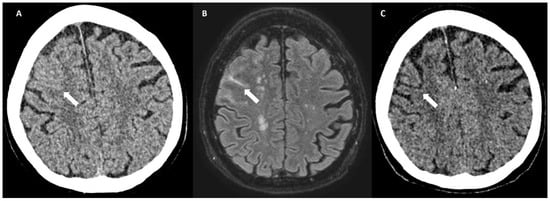

5.1.3. Convexity Subarachnoid Hemorrhage

5.1.4. Cortical Superficial Siderosis

6.2. Subarachnoid Extension of Lobar Hemorrhage

6.3. DWI Lesions

6.6. Cortical Calcifications